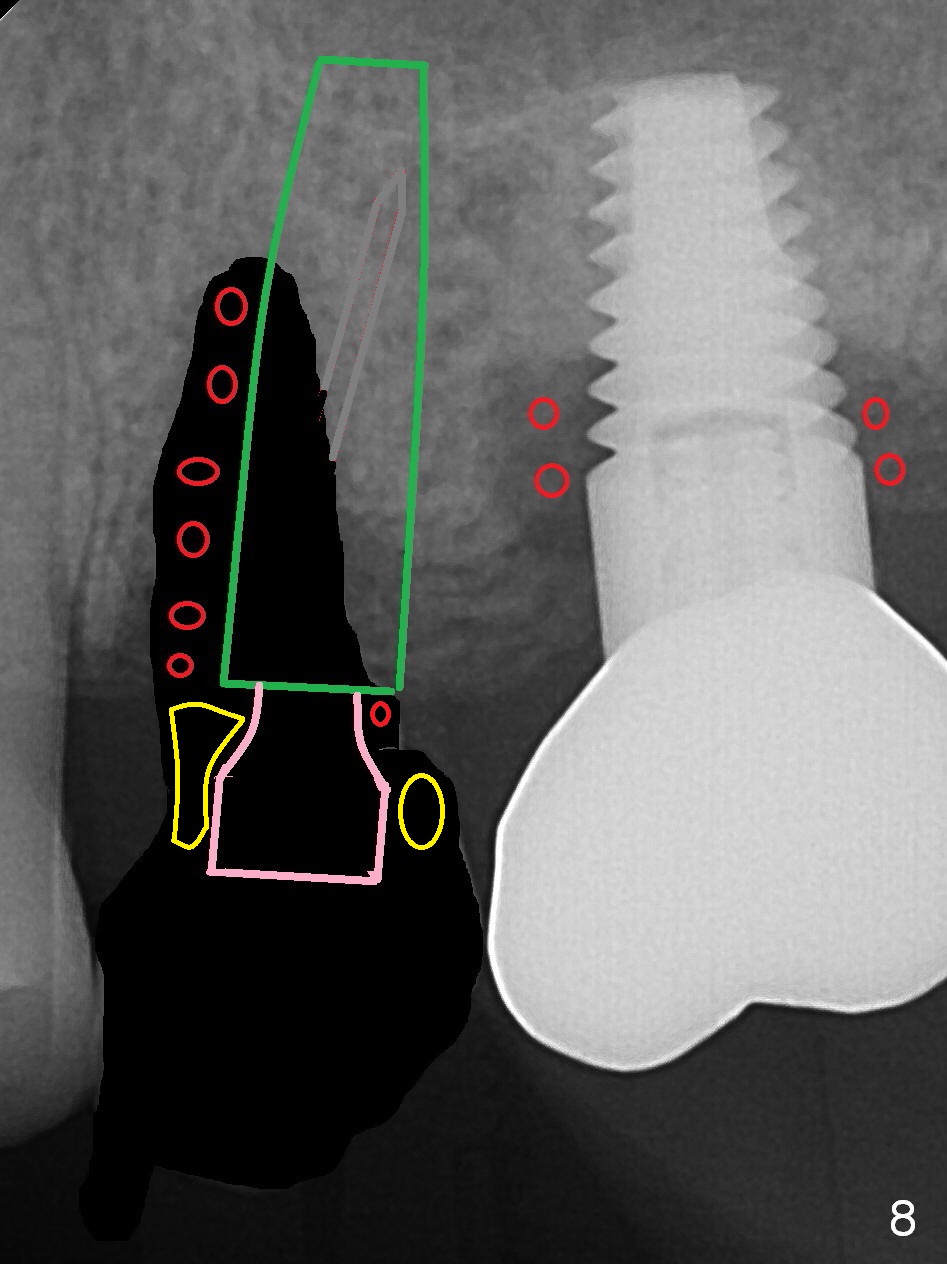

To compensate for bruxism, the implant at #13 should be as large and long as possible.  After extraction (Metronidazole), take PVS impression of the socket.  Start osteotomy in the distal wall of the socket (Fig.7 red).  The initial depth is 11 mm (gingival level).  Increase the depth once the trajectory is confirmed (Fig.9).  After implant placement (Fig.8 green), place bone graft (red circles) in the mesial portion of the socket as well as in the coronal portion of the implant at #14 (incision).  Use a healing abutment (pink), collagen plug (yellow) and suture to close the socket opening.